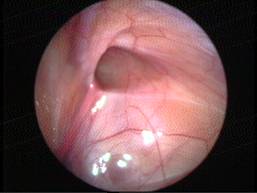

Acute Scrotum

Torsion Testis (Pre and Per operative photo)